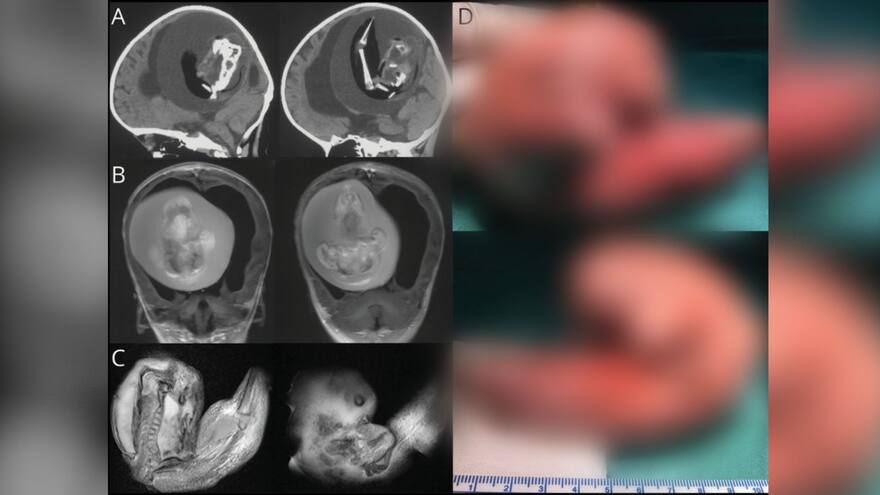

Fetus in fetus